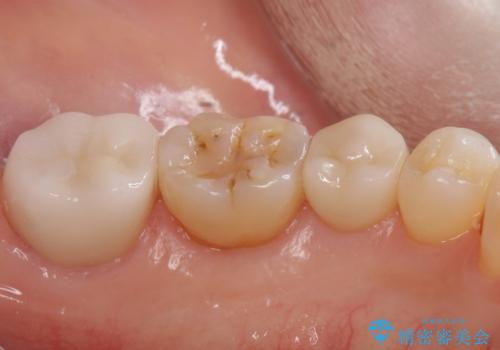

- 出産して落ち着いたから虫歯のチェックをしてほしいとのことで来院されました。

左下の奥歯に詰まっている樹脂の周辺が虫歯になっていたため、治療を進めていくこととなしました。

今回の場合、虫歯の大きさが大きく本来であれば歯茎に対しても治療をすることが検討されケースですが、ご希望されなかったため被せ物のみでの治療となりました。